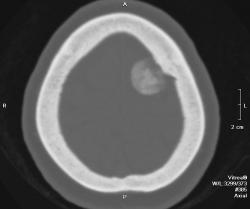

Полностью обызвествленная менингиома теменной области (красная стрелка). В прилегающей кости узурация (зеленые стрелки) и небольшой гиперостоз в виде клюва (голубая стрелка). Небольшой масс-эффект - крыша левого бокового желудочка поддавлена (желтая стрелка), субарахноидальные щели слева немного уже, чем справа. Перифокального отека нет - признак доброкачественности образования. Отек при менингиоме может развиться при очень больших размерах образования или при малигнизации. Пациентка жалуется на головные боли. На снимках черепа ничего необычного нет.